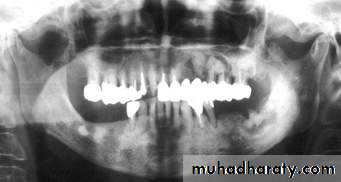

Fibro-cemento-osseous Lesions

The term fibrocemento- osseous lesion are defined as skeletal disorders in which bone is replaced by fibrous tissue which in turn is replaced by mineralized tissue (bone and/or cementum) to a varying degree as the lesions age.Although these lesions are radiolucent in their early stages, they are commonly seen clinically as variably radiopaque lesions.

Fibrous Dysplasia

Fibrous dysplasia is considered to represent a developmental tumour-like lesion. Most cases (approx. 80%) are monostotic (limited to a single bone, often the jaw).

• Shape: Round.

•Outline: — Poorly defined

— Not corticated.

Radiodensity: — Initially radiolucent

— Gradually becomes opaque to produce the typical ground glass, orange peel and finger print appearances resulting from superimposition of many fine, poorly-calcified bone trabeculae arranged in a disorganized fashion.

— Continuing to become more opaque with age.

Florid cemento-osseous dysplasia

Shape: — Multiple— Round, but frequently coalesce

Outline: — Smooth

— Moderately well defined

— Occasionally corticated.

Radiodensity: — Early stage — multiple Radiolucencies

— Intermediate stage — multiple radiolucencies with gradually increasing patchy internal opacities

— Late stage — multiple irregular dense radiopacities with individual lesions, sometimes surrounded by a thin radiolucent line.